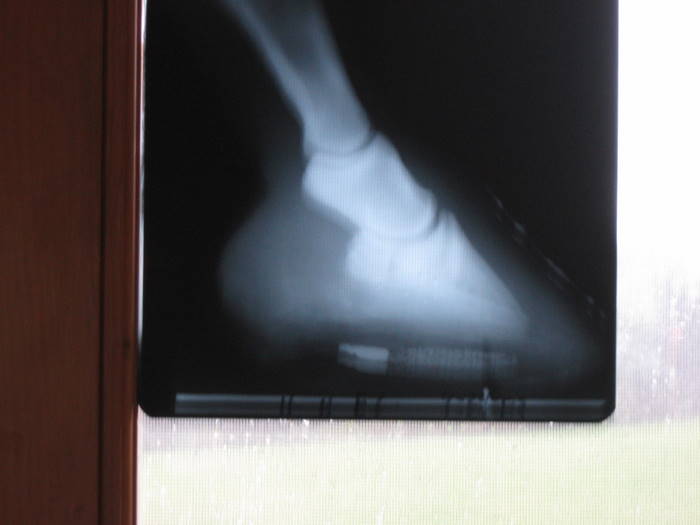

Here are his x-rays from 2007 a couple mos. after founder.

Here are x-rays from late April of this year

I don't know if that might help or not.

Thanks Angie, I believe she is right, he did take a lot of wall vertically, but it was all stretched out. He was sore before the trim, but not terribly.

He foundered twice. Once in 2005, and last year. He is VERY thin soled. Rotation was approx 8 degrees in both according to vet. And I believe she did see bruising, not the whole sole, but right at the tip by the toe the rest is betadine. UGHHH I imagine that is where the coffin bone is. I noticed it in one of the pics I didn't post, I think the betadine made it more obvious, I didn't see it before applying it. I will show you that pic.